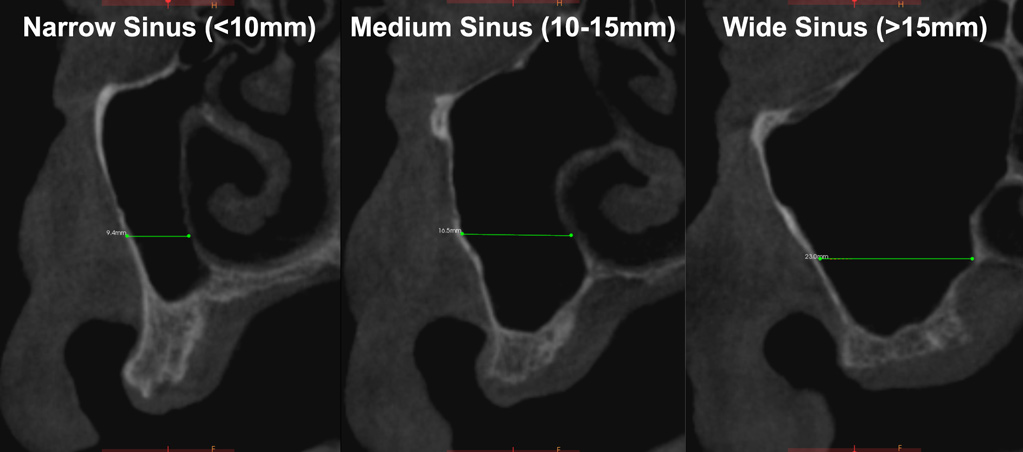

Fig 4. Cone-beam computed tomography of morphological size differences between narrow (<10 mm) (left), medium (10 mm to 15 mm) (center), and wide (>15 mm) (right) sinuses. The bucco-palatal distance is a predictable gauge for determining when to use PRF alone versus in combination with a bone grafting material.

One reported limitation of using PRF alone for sinus augmentation procedures is its use in wide sinuses. Avila et al demonstrated that lateral sinus augmentation procedures performed with an allograft in narrow sinuses (<10 mm) and medium sinuses (10 mm to 15 mm) demonstrated roughly three times more vital bone after a 6-month healing period when compared with wide sinuses (>15 mm) (Figure 4).24 In response to these findings and the clinical experiences of numerous oral surgeons using PRF alone for sinus augmentation procedures, it has been recommended that sinuses >15 mm be regenerated in a combination approach with a bone grafting material. Therefore, all sinuses greater than 15 mm should be regenerated using PRF cut into small fragments with a bone grafting material (Figure 5 and Figure 6).

For narrow sinuses (<10 mm), PRF alone has been shown to lead to high success rates with predictable new bone formation taking place in the sinus routinely. Great interest remains, however, in investigating sinus augmentation procedures in medium sinuses, those between 10 mm and 15 mm. While reports and clinical case presentations have shown that PRF alone can be used in such cases, caution must be advised. Additional surgical modalities, such as new (osseodensification) surgical burs or sinus elevation kits, may be employed to optimize implant bed preparation and primary stability of implants (Figure 7 and Figure 8). Such strategies may be combined with PRF to enhance its use as a sole grafting material in slightly wider sinuses. Nevertheless, further research is necessary before such recommendations can be deemed predictable.

A decision-making flow chart is provided in Figure 9. If the sinus is <10 mm in width, PRF alone may be used to predictably regenerate it. When the sinus is >15 mm, PRF combined with a bone grafting material is advised. When the bucco-palatal dimension is between 10 mm and 15 mm, though it is advisable to combine PRF with a bone grafting material, the clinician's experience and the surgical protocols used may indicate the regenerative procedure. Nevertheless, future research is eminently needed to determine optimal conditions to further characterize when to use PRF alone versus in combination with a bone grafting material. Conservative, predictable protocols, as suggested in Figure 9, are always recommended.